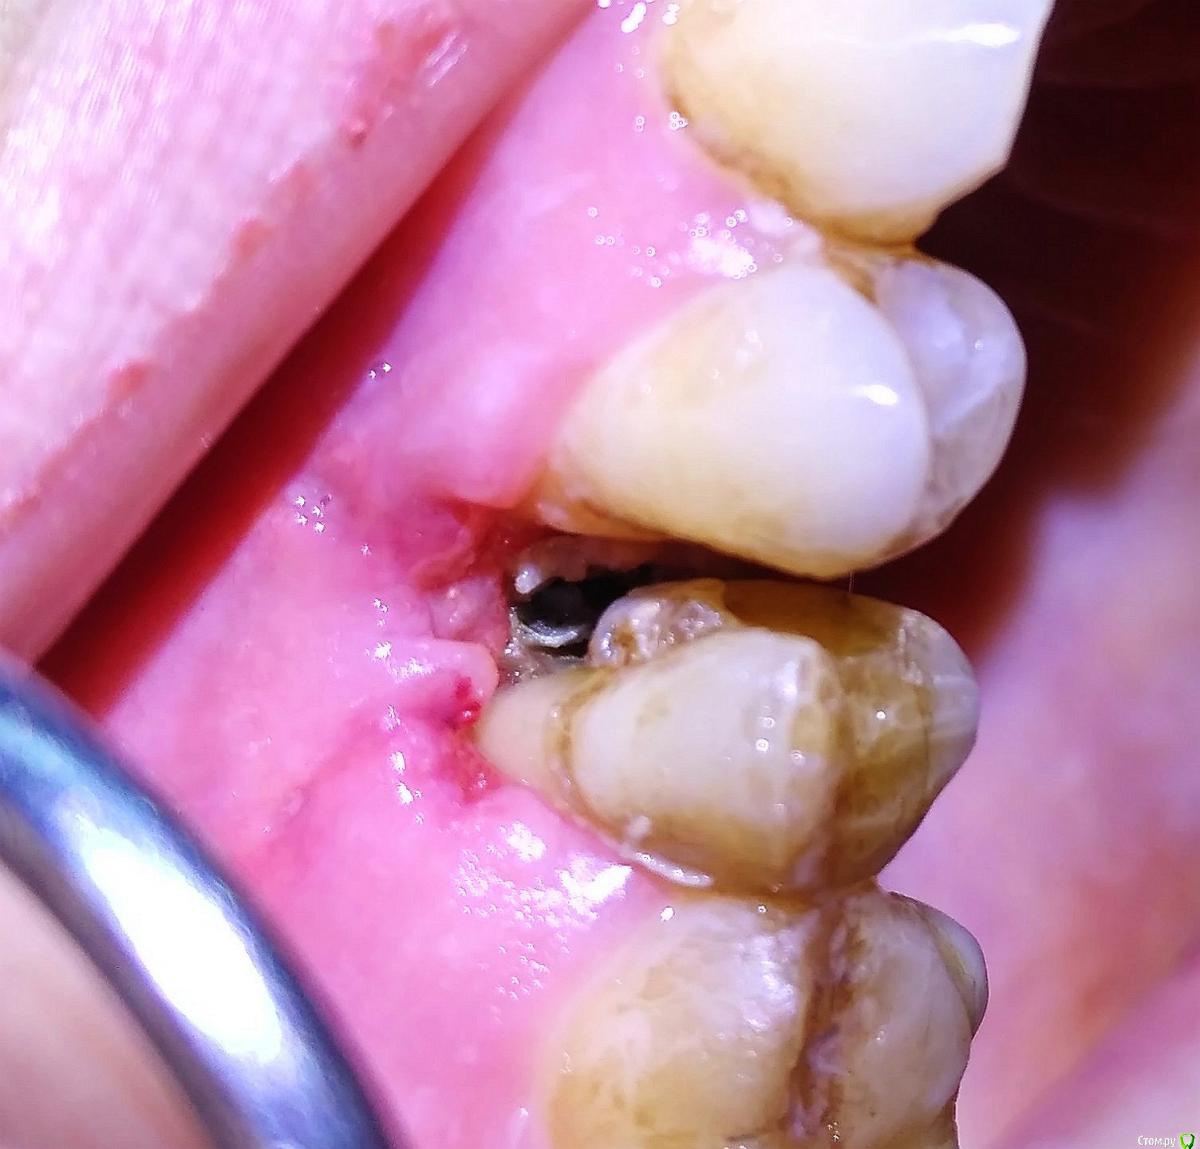

indie Опубликовано 19 сентября, 2016 Поделиться Опубликовано 19 сентября, 2016 Здравствуйте, колени. Сегодня на консультацию пришла пациентка, с жалобами на просевшую десну, оголения корня , неприятный запах между зубами 14 15. Симптомы появились в апреле месяце, после лечения корневых каналов в 15, в процессе которого пациентке, скорее всего, использовали Девит (врач сказал ,что препарат безвредный, русский, даже беременным так делают, наложили на 2 нед., болело еще на 2 недели). Дефект на зубе 15 по второму класу. Зубы не подвижны. Есть ОПТГ, но там ничего все ровно не видно, кроме нависающего. Визуально фото прилагаю. С причиной все понятно, а вот тактика, не совсем ясна. Ну смущает тот факт, що длится это все уже около 5 месяцев, и за это время организм не справился с процесом. Пациентка регулярно полощет хлоргекседином, ей прикладали туда риб'ячий жир, кололи антибиотики + системно, что-то подшивали. В конце предложили удалить зуб. Что, как мне кажется , нужно. 1.Убрать нависающий край, 2. кюретаж некротизированой ткани, солкосерил, ждать эпителизации. 3. Системно антибиотик+НПВС+ антигистаминные. (последние может ненужно?) Вопросы - Черная кость это секвестр? Это нужно убирать до здоровой кости? Кость можна твердосплавом убрать с охлаждением само собой. PS/ Я бы отправил к хирургам, но она уже там была, что-то делали, хотят уже 15 удалять. Ссылка на комментарий

vse32 Опубликовано 19 сентября, 2016 Поделиться Опубликовано 19 сентября, 2016 1.Убрать нависающий край, 2. кюретаж некротизированой ткани, солкосерил, ждать эпителизации. Согласна Черная кость это секвестр? Это нужно убирать до здоровой кости? Да.Когда у меня был такой пациент - все убралось экскаватором и кюретажной ложкой.Только потом все равно придется хирургам отдать, что бы восстановить высоту костного гребня и пластика десны. Ссылка на комментарий

Kolchanov Опубликовано 19 сентября, 2016 Поделиться Опубликовано 19 сентября, 2016 Да, там секвестр мешает зажить. Убрать его, кюретаж, сделать нормальные пломбы с контактом и т.д. Теоретически возможна какая-то пародонтология, но практически х.з. Ссылка на комментарий

indie Опубликовано 19 сентября, 2016 Автор Поделиться Опубликовано 19 сентября, 2016 Да, там секвестр мешает зажить. Убрать его, кюретаж, сделать нормальные пломбы с контактом и т.д. Теоретически возможна какая-то пародонтология, но практически х.з.Да там уже что-то парадонтировали, результат Вы видите. Это станом на "6 часов назад". За ответ спасибо. Ссылка на комментарий

Юлия Сергеевна 85 Опубликовано 21 сентября, 2016 Поделиться Опубликовано 21 сентября, 2016 Хм...у нас брали посев с такой же ситуации с таким же зубом..там актиномикоз)) Ссылка на комментарий